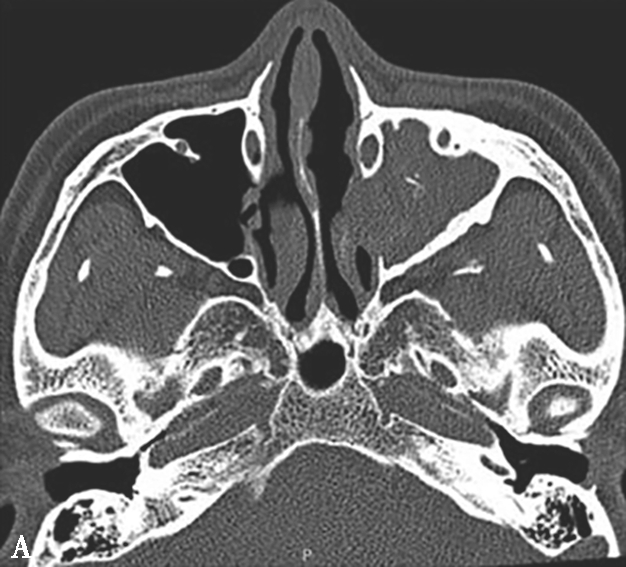

图1-3-19 急性鼻窦炎

A.CT横断面骨窗,示右侧上颌窦内软组织密度影,可见气-液平面;B、C.横断面及冠状面骨窗,示右侧上颌窦黏膜增厚

4.CT表现

①平扫表现:鼻窦黏膜增厚,伴黏液或脓液聚集时,可见气-液平面(图1-3-19)。严重者黏膜显著增厚,渗出液使窦腔实变,内夹杂气泡影。若感染不及时控制,窦壁骨质吸收、破坏,易形成骨髓炎,或向邻近结构蔓延引起蜂窝织炎。②增强扫描表现:边缘黏膜明显强化。